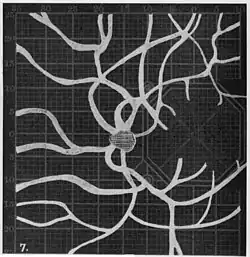

Angioscotomas were first discovered and mapped out by John Norris Evans (1891-02-28--1953-04-08)[2] in 1926, who coined the term angioscotometry to describe the painstaking charting of the scotoma of the retinal blood vessels by manual perimetry. He seated each subject in a seat in a dark setting, and tested whether they could see a tiny bright test object placed at various locations.[3] Using a 1.5 mm white disk, Evans reported intricate branch‑like scotomas that mirrored the arteries and veins emerging from the optic disc, with a full map requiring up to 2 hours to complete. He plotted this for subjects under various conditions, such as while holding breath, with glaucoma, etc. A year later, he confirmed that only short stump‑like scotomas had been noticed previously, some further data plotted with a smaller 1 mm stimuli, and under varying conditions on the subject.[4] He published a monograph on this in 1938 in which he described its use in assisting diagnosis of various conditions, such as retinal edema, glaucoma, optic neuritis, etc.[5]

In the 1940s there were further developments. Evans reviewed the state of research in 1942.[6] In 1945, Welt designed a portable campimeter and linked the size of both the blind spot and the angioscotoma to retinal arterial pressure.[7] In the same year, Weekers and Humblet published detailed tracings that overlaid vessel photographs onto Bjerrum screen plots, firmly establishing the one‑to‑one correspondence between vascular anatomy and scotoma shape.[8]

Using eccentric fixation, the more nasal parts of the angioscotoma can be plotted. -

1. Pressure on globe shows only stumps of large vessels. 2. Holding the breath causes similar effect; also 3. Holding the head low. 4. Pressure on opposite eye widens arteries and still more veins, 5. Pressure on the carotid produces no definite effect. 6. Looking thru red glass brings out finer vessels. -